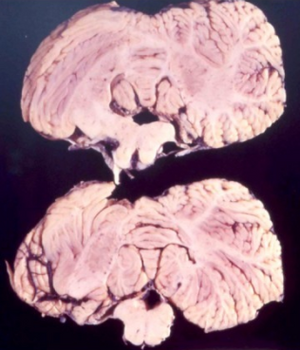

Studies from kuru infected individuals have revealed information explaining the effects that the disease can have on the brain. In the early stages of the disease, infected individuals may experience withdrawal, incoordination, tremors, and curling of the toes and feet.[17] To understand these difficulties in balance and coordination, studies were conducted to analyze the brain of kuru infected individuals. These studies by Klatzo et al., found that neurons in a kuru infected brain were abnormally small and lighter in color compared to their healthy counterparts.[17] Affected neurons appear "moth-eaten" due to their characteristic deformations. [17] These abnormalities in the neurons of the brain infected by kuru were similar to those with Creutzfeldt-Jakob disease (CJD).[17]